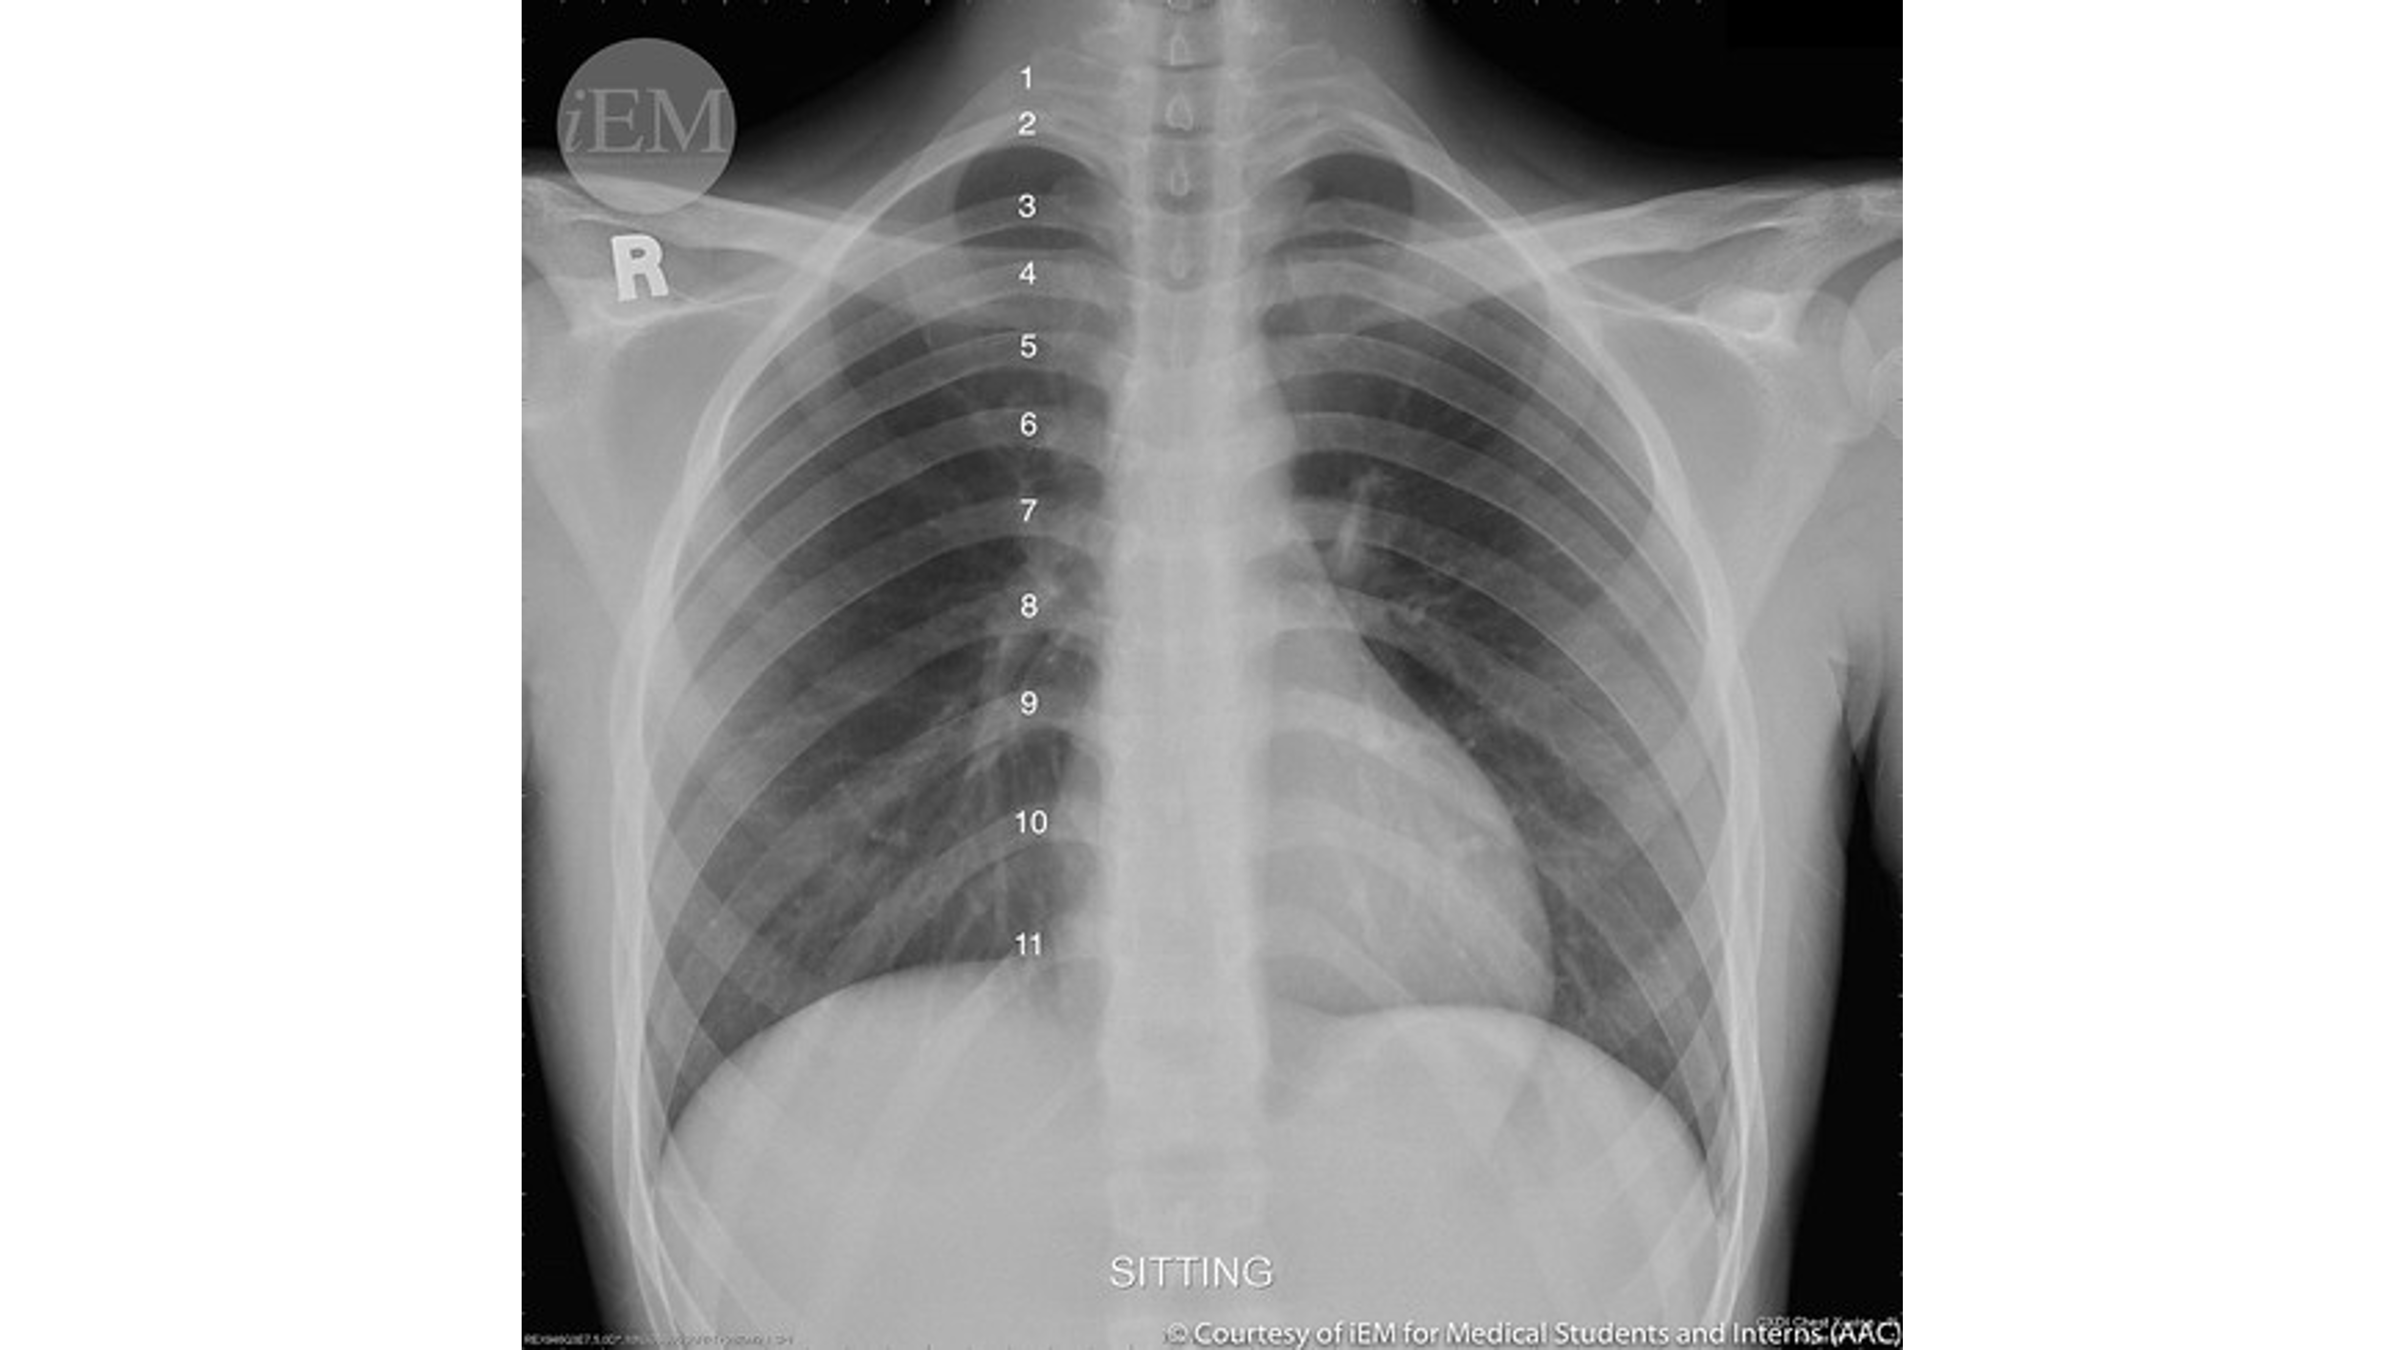

Visualization of more than __ ribs on CXR indicates adequate inspiratory effort.

More than 7

Name the mediastinal contours according to the numbers

1- superior vena cava

2- right atrium

3- inferior vena cava

4- aortic arch or knob

5- left pulmonary trunk

6- left pulmonary artery

7- left atrium

8- left ventricle

9- left cardiophrenic angle

Name the structures according to number